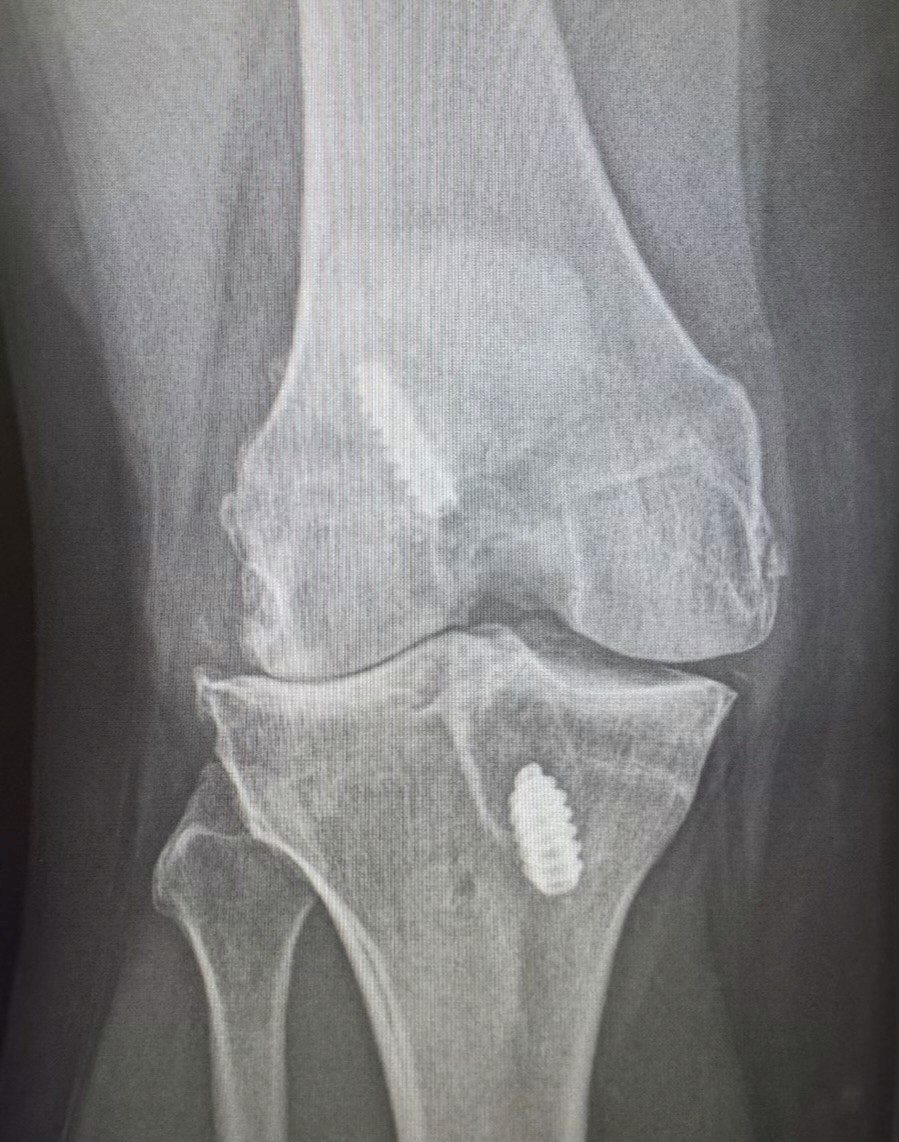

What about scans and X-rays ?

Scans are snapshots, not predictions.

They show:

• structure, not pain

• anatomy, not function

• change, not destiny

An MRI or X-ray does not tell you:

• how bad your pain will be

• whether things will worsen

• whether surgery is inevitable

Your symptoms, function, and quality of life matter far more.